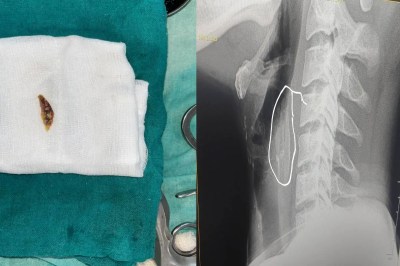

गले में फंसी चिकन के लेग पीस की हड्डी, दर्द से छटपटा रहे युवक की करनी पड़ी सर्जरी

mp news: मध्यप्रदेश के शाजापुर में एक युवक की जान उस वक्त खतरे में पड़ गई जब उसके गले में चिकन की हड्डी फंस गई। शाजापुर जिला अस्पताल में 24 वर्षीय युवक कन्हैया लाल की समय रहते डॉक्टरों ने सर्जरी की जिसके कारण उसकी जान बच गई। परिजन के मुताबिक चिकन खाने के बाद कन्हैया को सांस लेने और कुछ भी बोलने में काफी दिक्कत हो रही थी और वो दर्द से छटपटाने लगा था जिसके कारण वो उसे तुरंत अस्पताल लेकर आए थे।

गले में फंसी चिकन की हड्डी

कन्हैया लाल के पिता दशरथ ने बताया कि वो कांच इलाके में रहते हैं। रविवार रात को चिकन खा रहे थे तभी अचानक हड्डी बेटे कन्हैया के गले में अटक गई। इसके बाद कन्हैया को सांस लेने, बोलने और कुछ भी निगलने में भारी दिक्कत होने लगी। वो दर्द से छटपटाने लगा तो उसे तुरंत शाजापुर जिला अस्पताल लेकर आए, जहां जांच करने पर डॉक्टरों ने बताया कि गले में चिकन की हड्डी फंस गई है। अस्पताल में तैनात ईएमटी डॉक्टर तेजपाल सिंह जादौन ने मामले की गंभीरता को समझते हुए तत्काल ऑपरेशन करने का निर्णय लिया। सावधानीपूर्वक की गई इस प्रक्रिया के बाद गले में फंसी हड्डी को सफलतापूर्वक बाहर निकाल लिया गया।

सर्जरी से बची जान

ऑपरेशन के बाद मरीज कन्हैया लाल की हालत में तेजी से सुधार हुआ और अब वह खतरे से बाहर बताए जा रहे हैं। कन्हैया लाल ने बताया कि रविवार रात को हड्डी फंसने के बाद उन्हें असहनीय दर्द और घुटन महसूस हो रही थी। सोमवार को जिला अस्पताल के डॉक्टरों और स्टाफ की तत्परता से उन्हें राहत मिली। परिजनों ने डॉक्टर तेजपाल सिंह जादौन और अस्पताल प्रशासन का आभार व्यक्त किया। अस्पताल में तैनात ईएमटी डॉक्टर तेजपाल सिंह जादौन ने आम जनता से अपील की है कि भोजन करते समय विशेष सावधानी बरतें। उन्होंने यह भी कहा कि इस तरह की किसी भी आपात स्थिति में तुरंत नजदीकी अस्पताल पहुंचें, ताकि समय पर उचित उपचार मिल सके और गंभीर परिणामों से बचा जा सके।